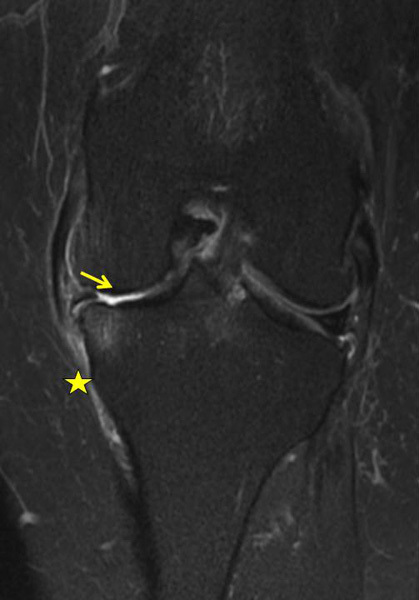

IRM du genou gauche pour une gonalgie gauche interne. Lésions dégénérative et luxation latérale du segment moyen du ménisque interne gauche avec disparition complète du cartilage tibial et condylien interne (flèche jaune. À noter, une ténosynovite des tendons de la patte d’oie (astérisque jaune).